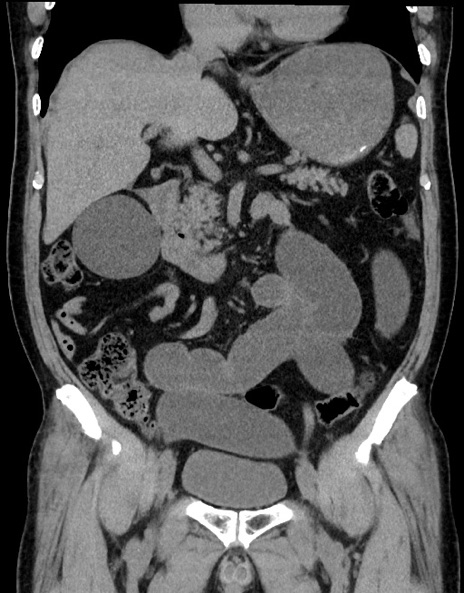

症例15(冠状断像)

【症例】70歳代男性

【主訴】腹痛

【現病歴】今朝から腹痛あり。全体的に痛い。特に左上の方。排ガスが今日はない。冷や汗が出る。

【既往歴】直腸癌術後

【身体所見】左側腹部〜上腹部に圧痛あり。腹膜刺激症状明らかなではない。軽度反跳痛。左下腹部に術後瘢痕あり。

【データ】WBC 7700、CRP 0.02